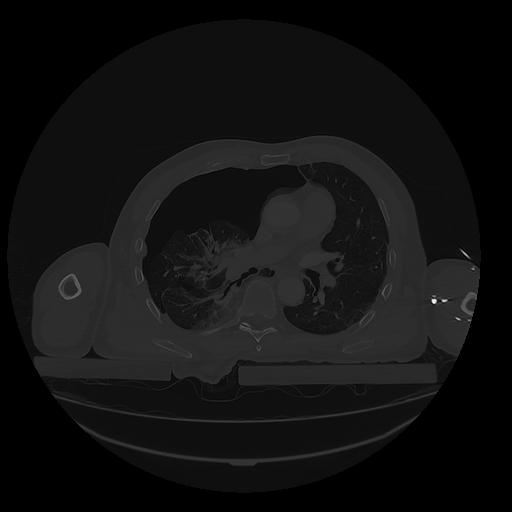

31 PULMON,CE,Vol,1.0,PULMON,,